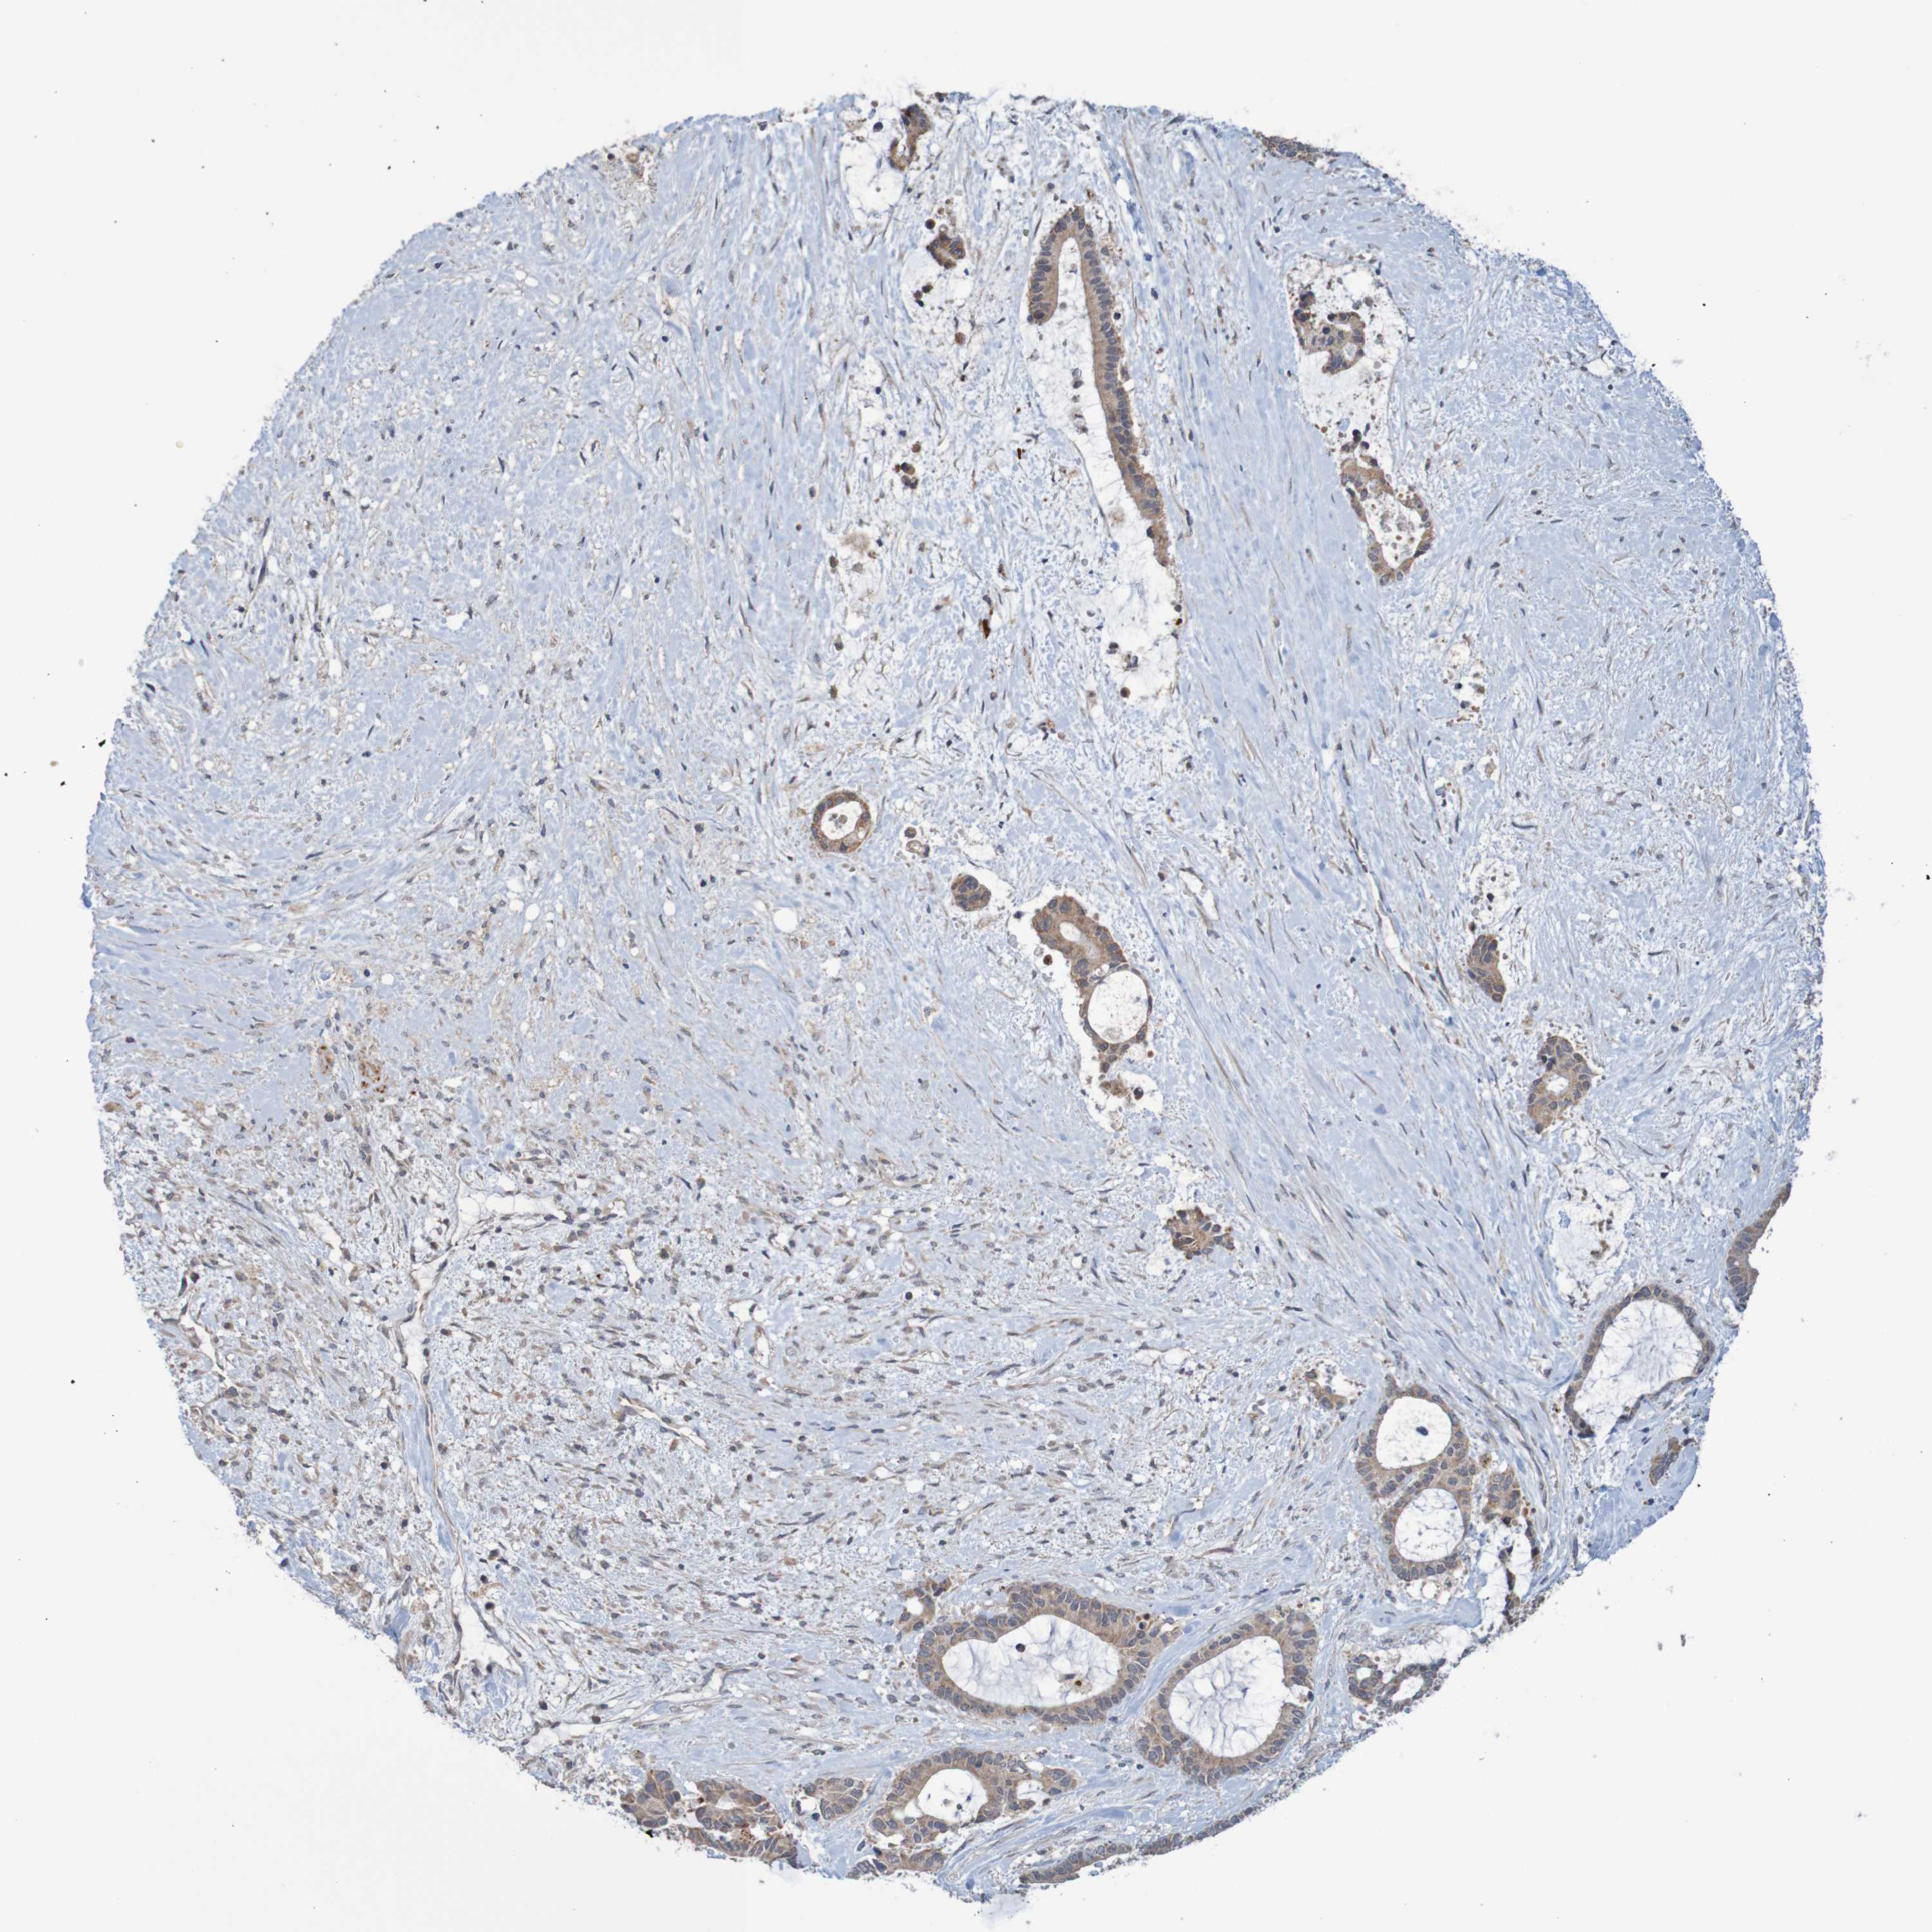

LIVER CANCER - Protein expressioni

A mouse-over function shows sample information and annotation data. Click on an image to view it in a full screen mode. Samples can be filtered based on level of antibody staining by selecting one or several of the following categories: high, medium, low and not detected. The assay and annotation is described here.

Note that samples used for immunohistochemistry by the Human Protein Atlas do not correspond to samples in the TCGA dataset.

Antibody stainingi

Antibody staining in the annotated cell types in the current human tissue is reported as not detected, low, medium, or high, based on conventional immunohistochemistry profiling in selected tissues. This score is based on the combination of the staining intensity and fraction of stained cells.

Each image is clickable and will lead to virtual microscopy that enables deeper exploration of all samples and also displays staining intensity scores, fraction scores and subcellular localization as well as patient and tissue information for each sample.

Read more

Antibody HPA012813

Staining

High

Medium

Low

Not detected

Intensity

Strong

Moderate

Weak

Negative

Quantity

>75%

75%-25%

<25%

None

Location

Nuclear

Cytoplasmic/membranous

Cytoplasmic/membranous,nuclear